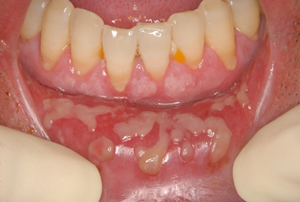

口腔内に照射した場合は必ず粘膜炎(粘膜のやけどに近い状態)が起こり、痛みが出現します。

これらの治療により、口腔粘膜が赤く腫れ気味になり、それとともに表面が少しでこぼことなり、粘膜の一部がはがれて潰瘍(かいよう)ができる場合もあります。

そうなると痛みも強くなり、食事も口からとることができないほどになることもあります。